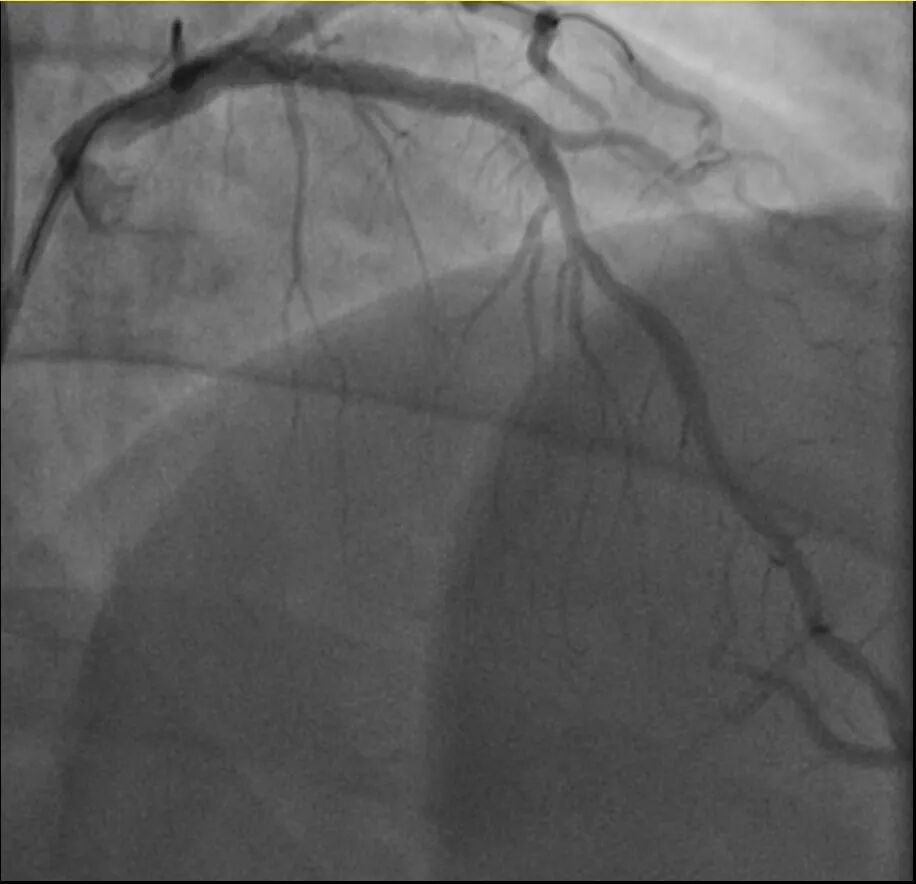

他的血糖一直偏高,服药后控制不佳,但年轻的钱先生并没有太上心。周末,他和孩子爬了一座山,隔天,钱先生就因突发胸骨中段压榨性疼痛被送到了急诊,最后被证实也是心梗——心脏三支主要血管之一回旋支远段次全闭塞。

浙江医院心血管内科翁莹政医师介绍,这位患者来院时血糖12.79mmol/L(正常空腹值应该在3.9~6.1mmol/L),甘油三酯也超标。三高(高血压、高血脂、高血糖)是导致动脉粥样硬化(包括心脏的冠状动脉)的主要危险因素。所幸经过汤益民团队的及时介入治疗,钱先生也转危为安。

介入治疗前后影像图